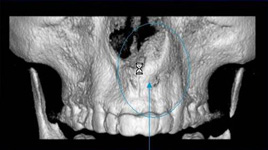

3D DVT - NewTom

Je speciální zubní digitální tříprostorový tomograf (3D), který umožňuje na základě jediného

snímkování vytvořit všechny typy RTG zobrazení, které jsou pro lékaře potřebné. Díky používané technologii tzv. „kuželového paprsku“ a speciálním senzorům je

výrazně zmenšená dávka záření - o více jak 80% proti klasickému CT vyšetření. To je významné zejména u dětí. Pomocí tohoto přístroje je možné zjisti skutečnou situaci v čelistních kostech pacienta tedy množství kosti - můžeme změřit skutečnou šířku i výšku kosti, i kvalitu kosti (hustotu) v místě uvažované implantace. 3D (tříprostorové) zobrazení umožňuje zvýšit prostorovou představu operatéra ještě před vlastní operací a zároveň pacientovi lépe objasnit a ukázat oblast plánovaného zavedení implantátu.

Pacient „neumí číst“ RTG snímky, ale díky 3D zobrazení vidí „svoji skutečnou čelist“

- např. jak je nízká či úzká, vidí průběh nervu nebo velikost čelistní dutiny, což mu umožní i pochopení nutnosti v některých případech provést pomocné zákroky ještě před vlastním zavedením implantátu (viz. kostní štěp, sinus lift, kostní granulát...).